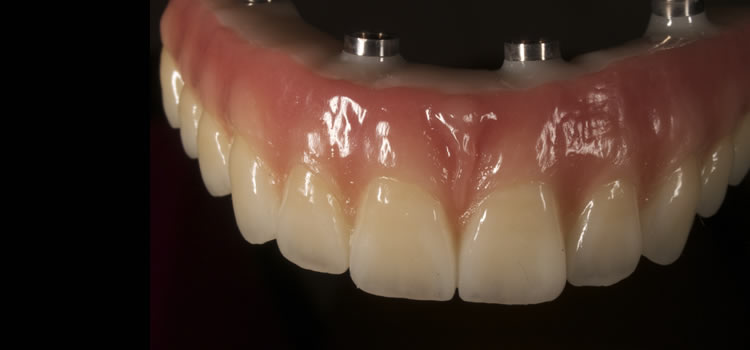

当クリニックのオールオン4は全てのケースで一辺倒に骨を削り人工歯肉を付ける従来のオールオン4治療とは異なります。精密な診査診断により、全顎的インプラント治療において人工歯肉を付けなくても可能な症例が5%〜10%あります。この術式を成功させる為には非常に高い技術力が必要です。